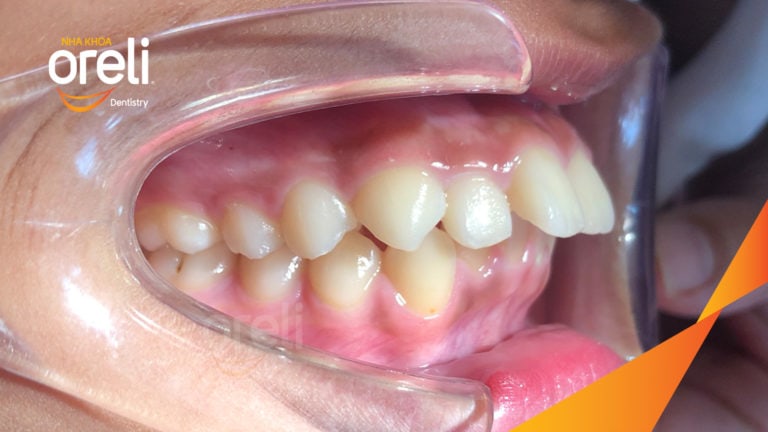

Ca niềng chỉnh cắn sâu không nhổ răng kết quả cười đẹp sau hơn hai năm tại Oreli Niềng răngCắn sâu Xem thêm